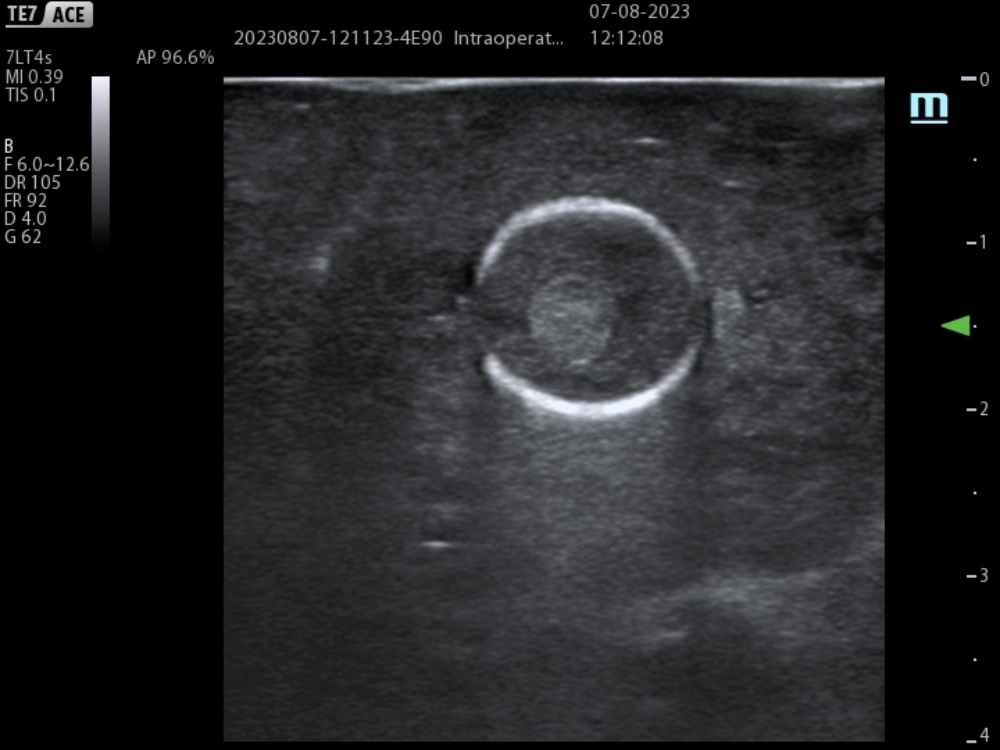

The patient underwent a right hepatectomy. In the transoperative period, we used intraoperative ultrasound with Mindray´s linear T-Shape probe 7LT4s ( Figure 3) and TE7 portable ultrasound system to mark the transection line just at the level of the middle suprahepatic vein, taking care to preserve the material used for suprahepatic venous deprivation (Figure 4 and 5).

non-crirrhotic-liver-fig4

Figure 4. Intraoperative ultrasound shows Amplatzer visible in branch of suprahepatic vein towards segment VIII.